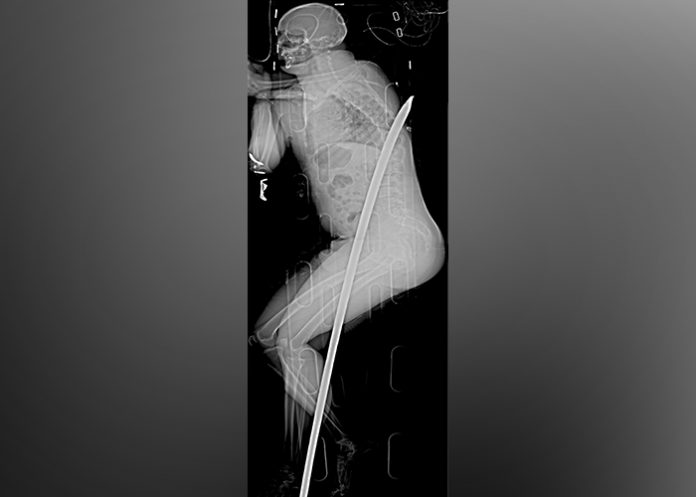

JOHANNESBURGO (AP) – Hace tres años, un sudafricano sufrió un accidente minero que casi lo mata: una varilla industrial lo penetró de un lado al otro del cuerpo, entrando entre sus piernas y saliendo por su espalda, justo debajo de su omóplato. Ahora Daniel de Wet se clasificó para correr el próximo domingo en el ultramaratón Camaradas.

De Wet perdió uno de sus riñones y sufrió otras lesiones internas por la palanca metálica de 1,8 metros (5,9 pies).

El terrible accidente ocurrió en enero de 2015, cuando cayó en la varilla en una mina en Carletonville, una zona minera de oro cerca de Johannesburgo. Con la palanca aún clavada, estuvo consciente mientras que subieron a la superficie en una camilla. Los rescatistas lo transportaron en avión a un hospital, donde los cirujanos retiraron la palanca. De húmedo fue dado de alta 19 días después.